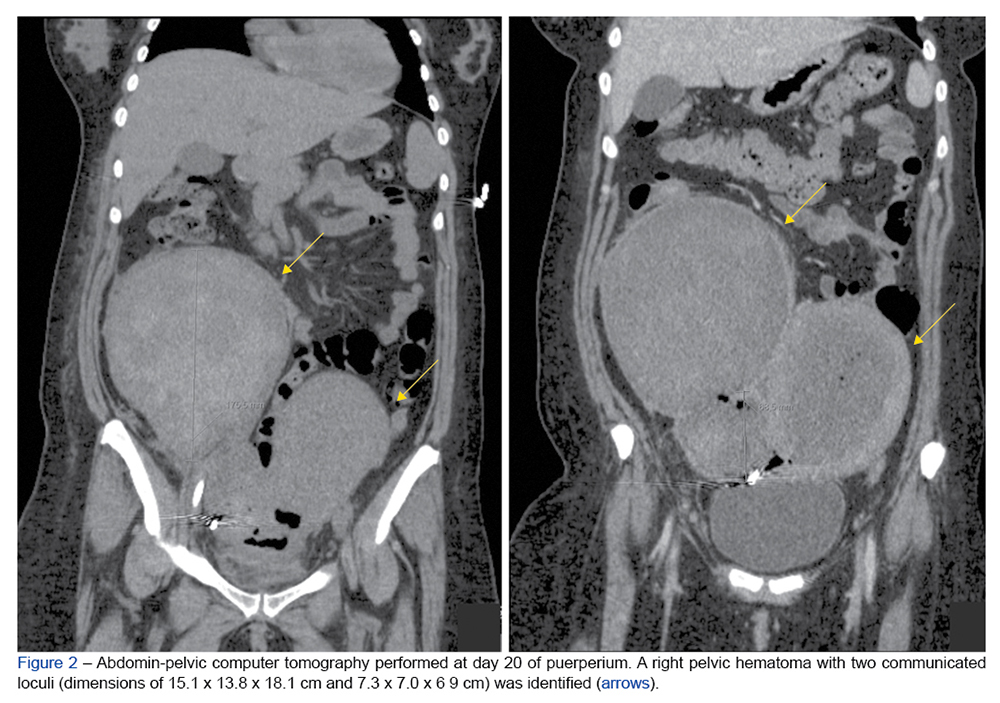

Inflammatory myofibroblastic tumour is a rare entity of indeterminate biological potential with a reduced tendency for recurrence and metastasis. Although it can arise...